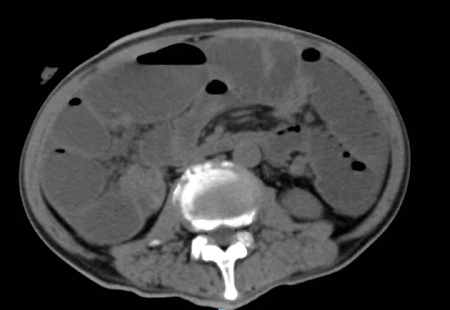

2022年5月的一个凌晨,一位93岁的老奶奶因为腹胀伴呕吐被送到了新龙泽院区急诊科,经过问诊和初步查体后,接诊医生考虑患者存在肠梗阻,立即为患者申请了急诊腹部CT检查,结果显示患者的升结肠存在一个巨大的肿物堵塞了肠腔。在给予补液和胃肠减压的同时,普外科立即对患者的病情进行了紧急评估和讨论。肿瘤导致患者出现肠梗阻,手术是唯一的解决方案,但患者高龄且身体非常瘦弱,围手术期发生肺部感染、心脑血管事件等并发症的概率非常高。普外科高鹏骥主任医师制定了急诊实施腹腔镜下右半结肠切除的手术方案,并在麻醉科和手术室医护团队的密切配合下顺利完成了手术。